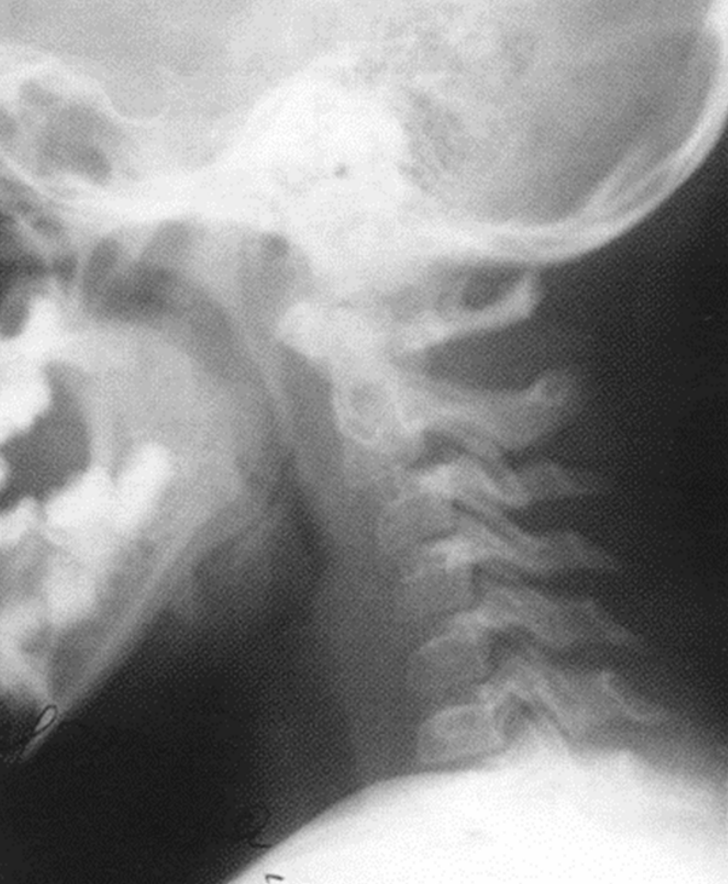

Боли в шее

и головные боли -